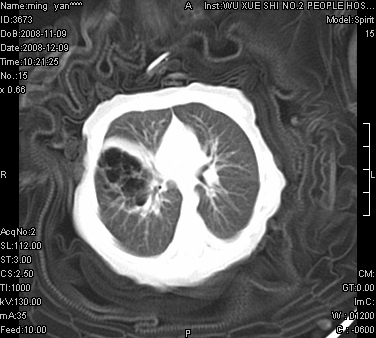

女.30天.咳嗽.喘3天.系三胞胎

考虑右肺下叶先天性肺囊肿,不除外合并右中叶肺发育不全

伴双肺感染

考虑右肺下叶先天性多发性肺囊肿可能。

考虑右肺下叶肺囊肿伴感染,右中叶节段实变或发育不全

这是一个先天性囊性腺瘤样畸形(congenital cystic adenomatid malformation,ccam),属于先天性肺发育异常,最近国外文献重新命名为先天性肺气道畸形(congenital pulmonary airway malformation,cpam),根据发生部位和畸形组织与气管、支气管的关系分成五型。本病以1岁以下婴儿多见,男性多于女性。病因为终末呼吸单元的异常增殖,形成多囊状结构。国内根据影响和病理表现分三型:ⅰ型为单个或多个大囊肿,直径大于2cm;ⅱ型为多个小囊肿,直径小于2cm;ⅲ型为大的非囊肿性病变,但显微镜下观察可见肿块由多发小囊组成(直径小于2mm)。本病可发生于肺内任何一部分,单侧肺占95%,中叶病变相对较少。